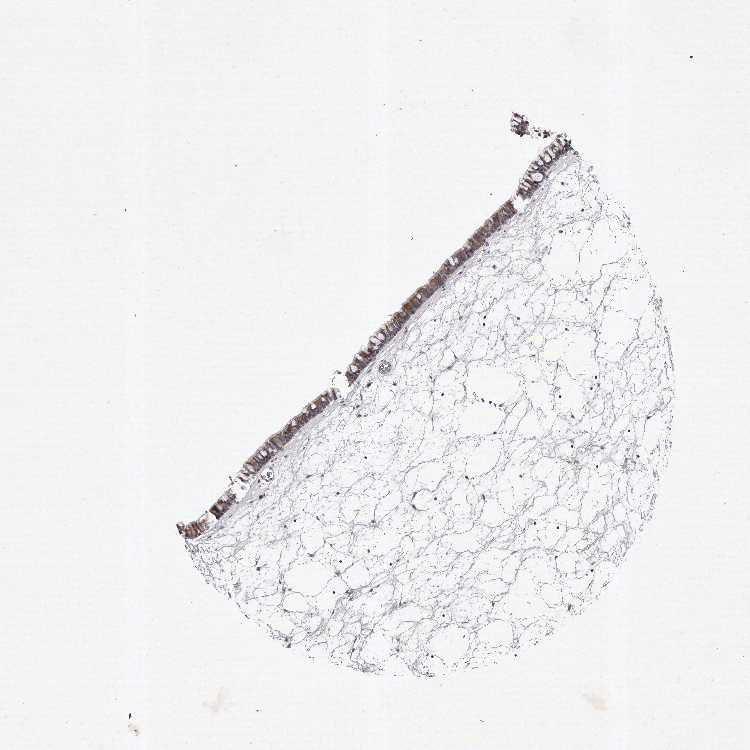

TISSUE PRIMARY DATA NASOPHARYNX Show tissue menu

NASOPHARYNX - Antibody stainingi

Antibody staining in the annotated cell types in the current human tissue is reported as not detected, low, medium, or high, based on conventional immunohistochemistry profiling in selected tissues. This score is based on the combination of the staining intensity and fraction of stained cells.

Each image is clickable and will lead to virtual microscopy that enables deeper exploration of all samples and also displays staining intensity scores, fraction scores and subcellular localization as well as patient and tissue information for each sample.

Antibody HPA029780Antibody HPA056488

Respiratory epithelial cells MediumMedium